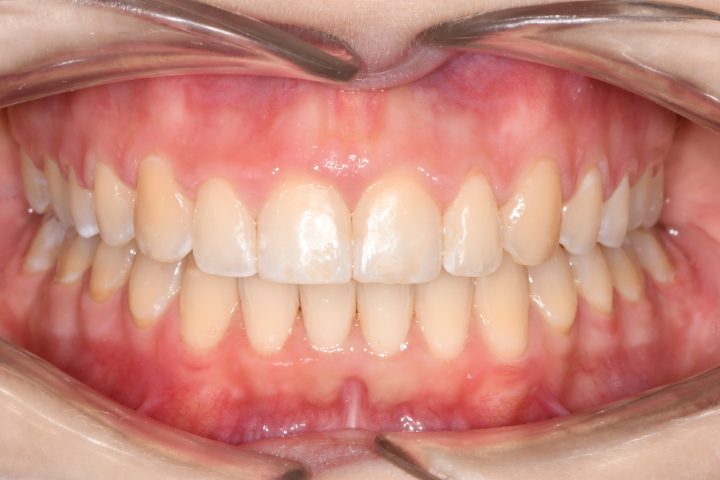

Az elmúlt évekből rengeteg szakmai referenciát tudnánk bemutatni, amelyek különböző fogszabályozási problémákat oldottak meg. Válogatva a több száz esetből, ezen az oldalon olyan képeket, információkat igyekeztünk bemutatni, amelyeknek a segítségével a jövőbeni pácienseinknek azt tudjuk üzenni: A Te fogsorod is lehet gyönyörű!

(Képeket a Pácienseink külön írásos beleegyezésével mutatjuk be!)